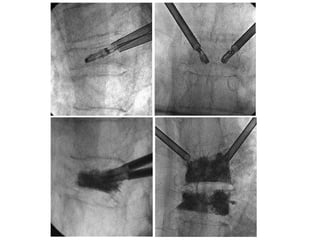

In most cases

we use a bilateral

approach with

one needle

through left and

another through

the right pedicle

Ready to inject cement

Once the needle passes the pedicle into the vertebral body, the

needle tip can be advanced to the junction between anterior

and middle third of the vertebral body.

Then the second needle is placed into the contralateral half of

Cement Injection

• Meticulous fluoroscopic monitoring during the

injection process.

• Liquefied cement is injected into the vertebral

body.

• Termination of injection.

– Cement in posterior 1/3 vertebral body on lateral

projection.

– Cement extruding into epidural, foraminal or

paraspinal veins.

– Significant disk space penetration.

– Posterior 1/3.

We use 1 ml syringes attached directly to the

bone biopsy needle to inject the cement.

Meticulous fluoroscopic control is important

for early detection of leakage.

Cement injection is the last step in all levels

Termination of injection ??

Cement in posterior 1/4 of vertebral body on

lateral projection

Cement extending outside vertebra